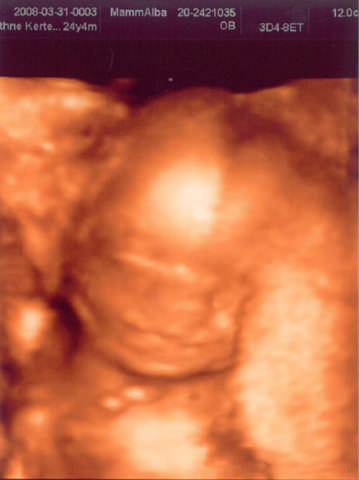

Szilvi, kis huncut Titababátok van. Roni mindenét megmutatta már nekünk. :)

Ja azt nem is írtam, jó nagy buksija van :shock:

RL kétszer is megmérte a buksiját, azt hitte, hogy rosszul nézte. :roll:

Kép az én kis Hercegemről